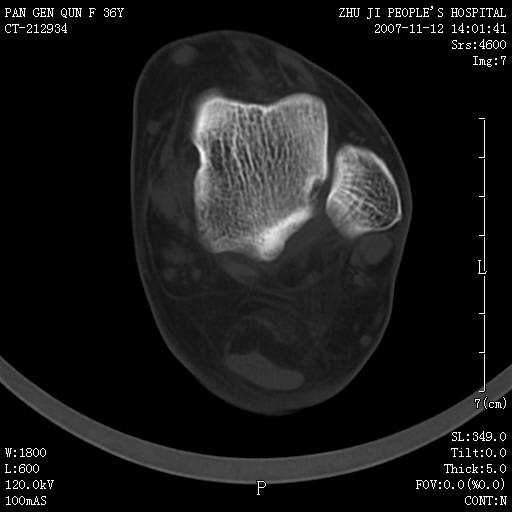

标题: CT10417:F36Y,跟骨跟腱附着处下方骨质密度影,请会诊. [打印本页]

标题: CT10417:F36Y,跟骨跟腱附着处下方骨质密度影,请会诊.

跟骨结节后部肿块半年,无明确外伤史,及红肿热痛.

骨软骨瘤

骨软骨瘤?

附丽病

附丽病:是指肌腱、关节囊、韧带于骨附着处的骨化和骨质侵蚀改变,常见于坐骨结节、髂骨嵴、坐骨耻骨支、股骨大小粗隆、跟骨结节等处。

x线表现为具有骨密度的细条索状影自骨面伸向附近的韧带、肌腱,宛如浓厚的胡须,以病变晚期更为明显,并有局部骨质侵蚀。

跟腱附着处骨化致骨化性肌炎。